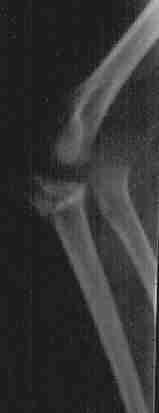

Fractura de codo izquierdo. Pablo, 4 años y medio La misma fractura, vista desde otro ángulo Reconstrucción del hueso (osteosíntesis) llevada a cabo tres días después Aspecto del hueso a los tres meses, después de retirar las piezas metálicas.

Aspecto del hueso a los tres meses, después de retirar las piezas metálicas.